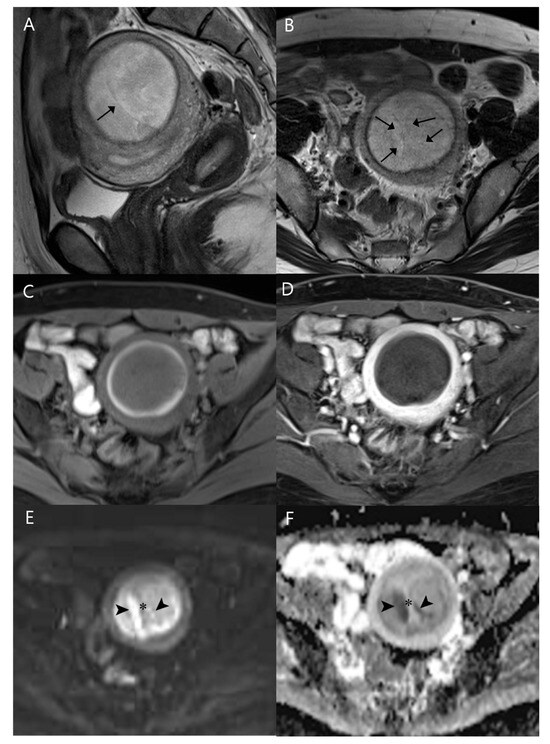

Low-Grade Endometrial Stromal Sarcoma: A Case Report of a Rare Uterine Malignancy Mimicking Degenerative Uterine Leiomyoma in a Nulliparous Woman

2. Case Report